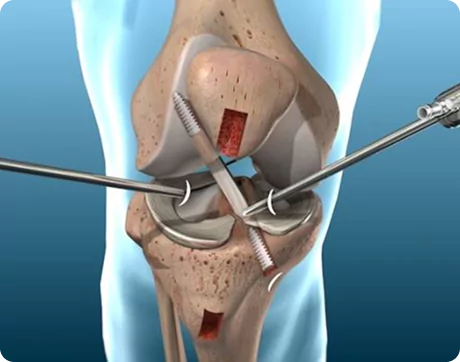

What Is Spine Surgery?

Spine surgery is a medical intervention aimed at treating conditions that affect the spinal column and spinal nerves. It becomes necessary when conservative treatments such as physiotherapy, medications, or injections fail to relieve persistent symptoms like chronic back pain, sciatica, or nerve compression.

The spine is a complex structure composed of vertebrae, discs, nerves, and ligaments. Problems in any of these areas can lead to severe pain, restricted movement, or neurological symptoms. Spine surgery helps to correct structural abnormalities, relieve pressure on spinal nerves, stabilise the spine, and restore function.